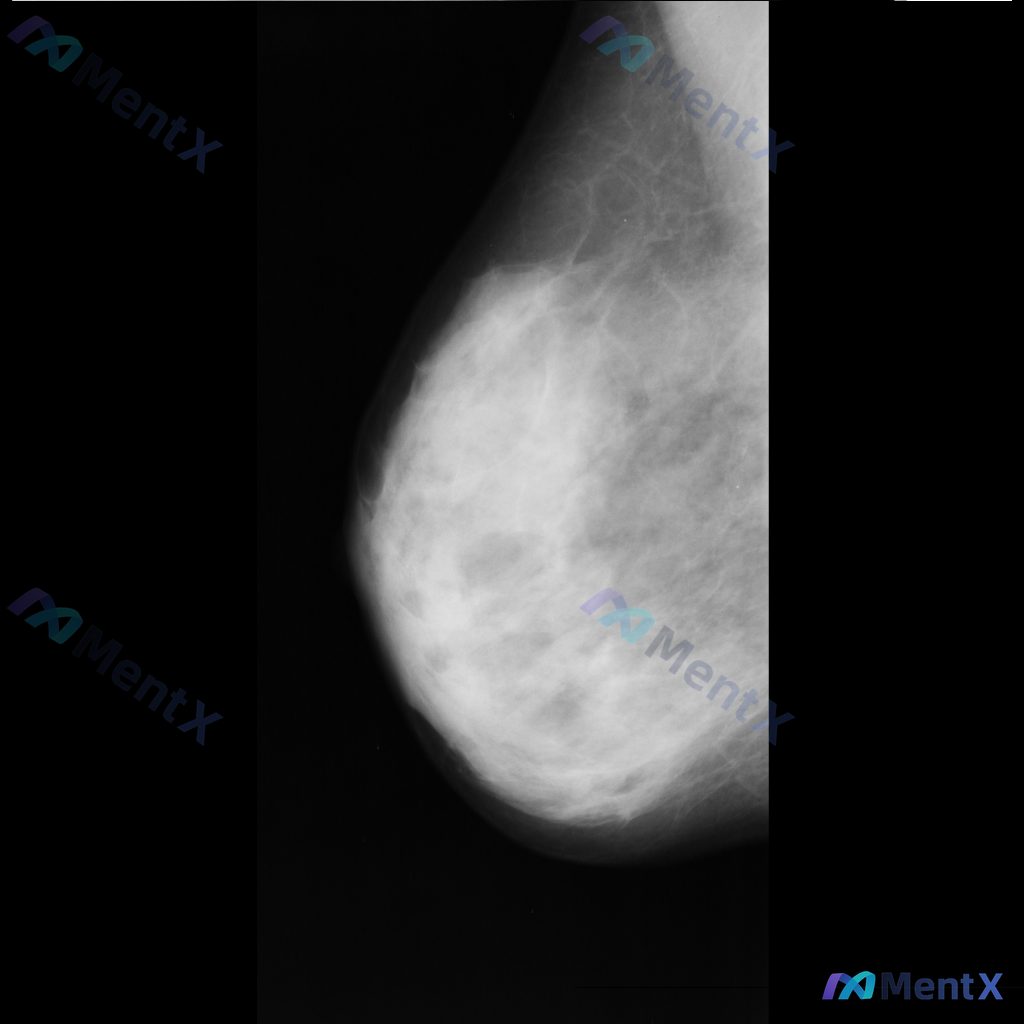

整理到一张乳腺钼靶影像资料,主要征象如下: - 图像中央偏右下方可见一处约5mm、密度相对较高的圆形或卵圆形致密影,边缘尚可; - 右上象限可见沿乳腺导管走行的一些粗大钙化影; - 中央偏下方也可见散在点状钙化,形态和分布无典型恶性特征; - 乳腺组织以纤维腺体为主,脂肪组织相对较少,属于致密影较多...

整理到一张单侧乳腺钼靶影像的读片资料,目前是单一体位图像,没有双侧对比。 影像表现整理 - 乳腺组织密度较高,属于多量腺体型或致密型背景 - 可见散在的钙化灶:图像中部偏下有数个点状或粗大钙化,形态不规则,但无典型恶性钙化的细小多形性、线样或分支状表现 - 乳腺下象限可见多个高密度圆形/卵圆形影,边...